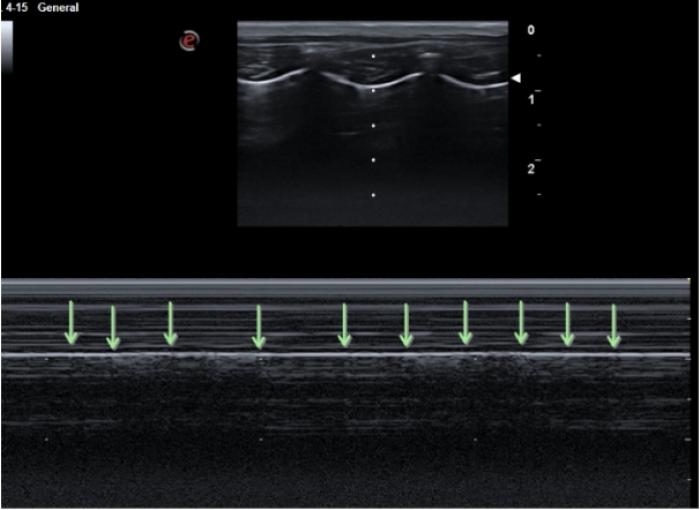

El signo de deslizamiento puede ser evaluado tanto en modo B como en modo M.

En caso de neumotórax severo con ocupación del receso costofrénico el signo de cortina se verá inalterado llamándose pseudo signo de cortina y siendo exactamente igual que el signo de cortina del paciente sano. En caso de neumotórax parcial, podemos ver el signo de cortina asincrónico, en el cual las vísceras abdominales se desplazan caudalmente en la inspiración y el signo de cortina lo hace cranealmente (al contrario que en el paciente sano) (Figura 8A-C).